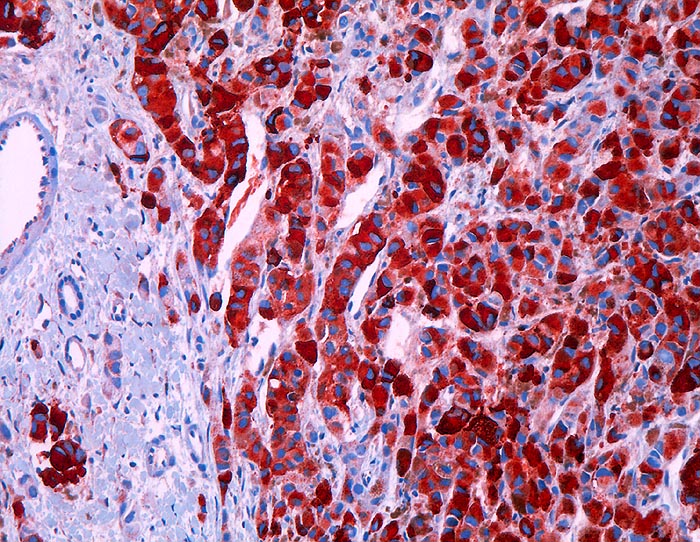

Malignes Melanom : Lebermetastase

Leber

Starke zytoplasmatische Positivität der Tumorzellen für HMB-45.

V.a. hepatozelluläres Karzinom.

Histologie

Immunhistochemie

HMB-45